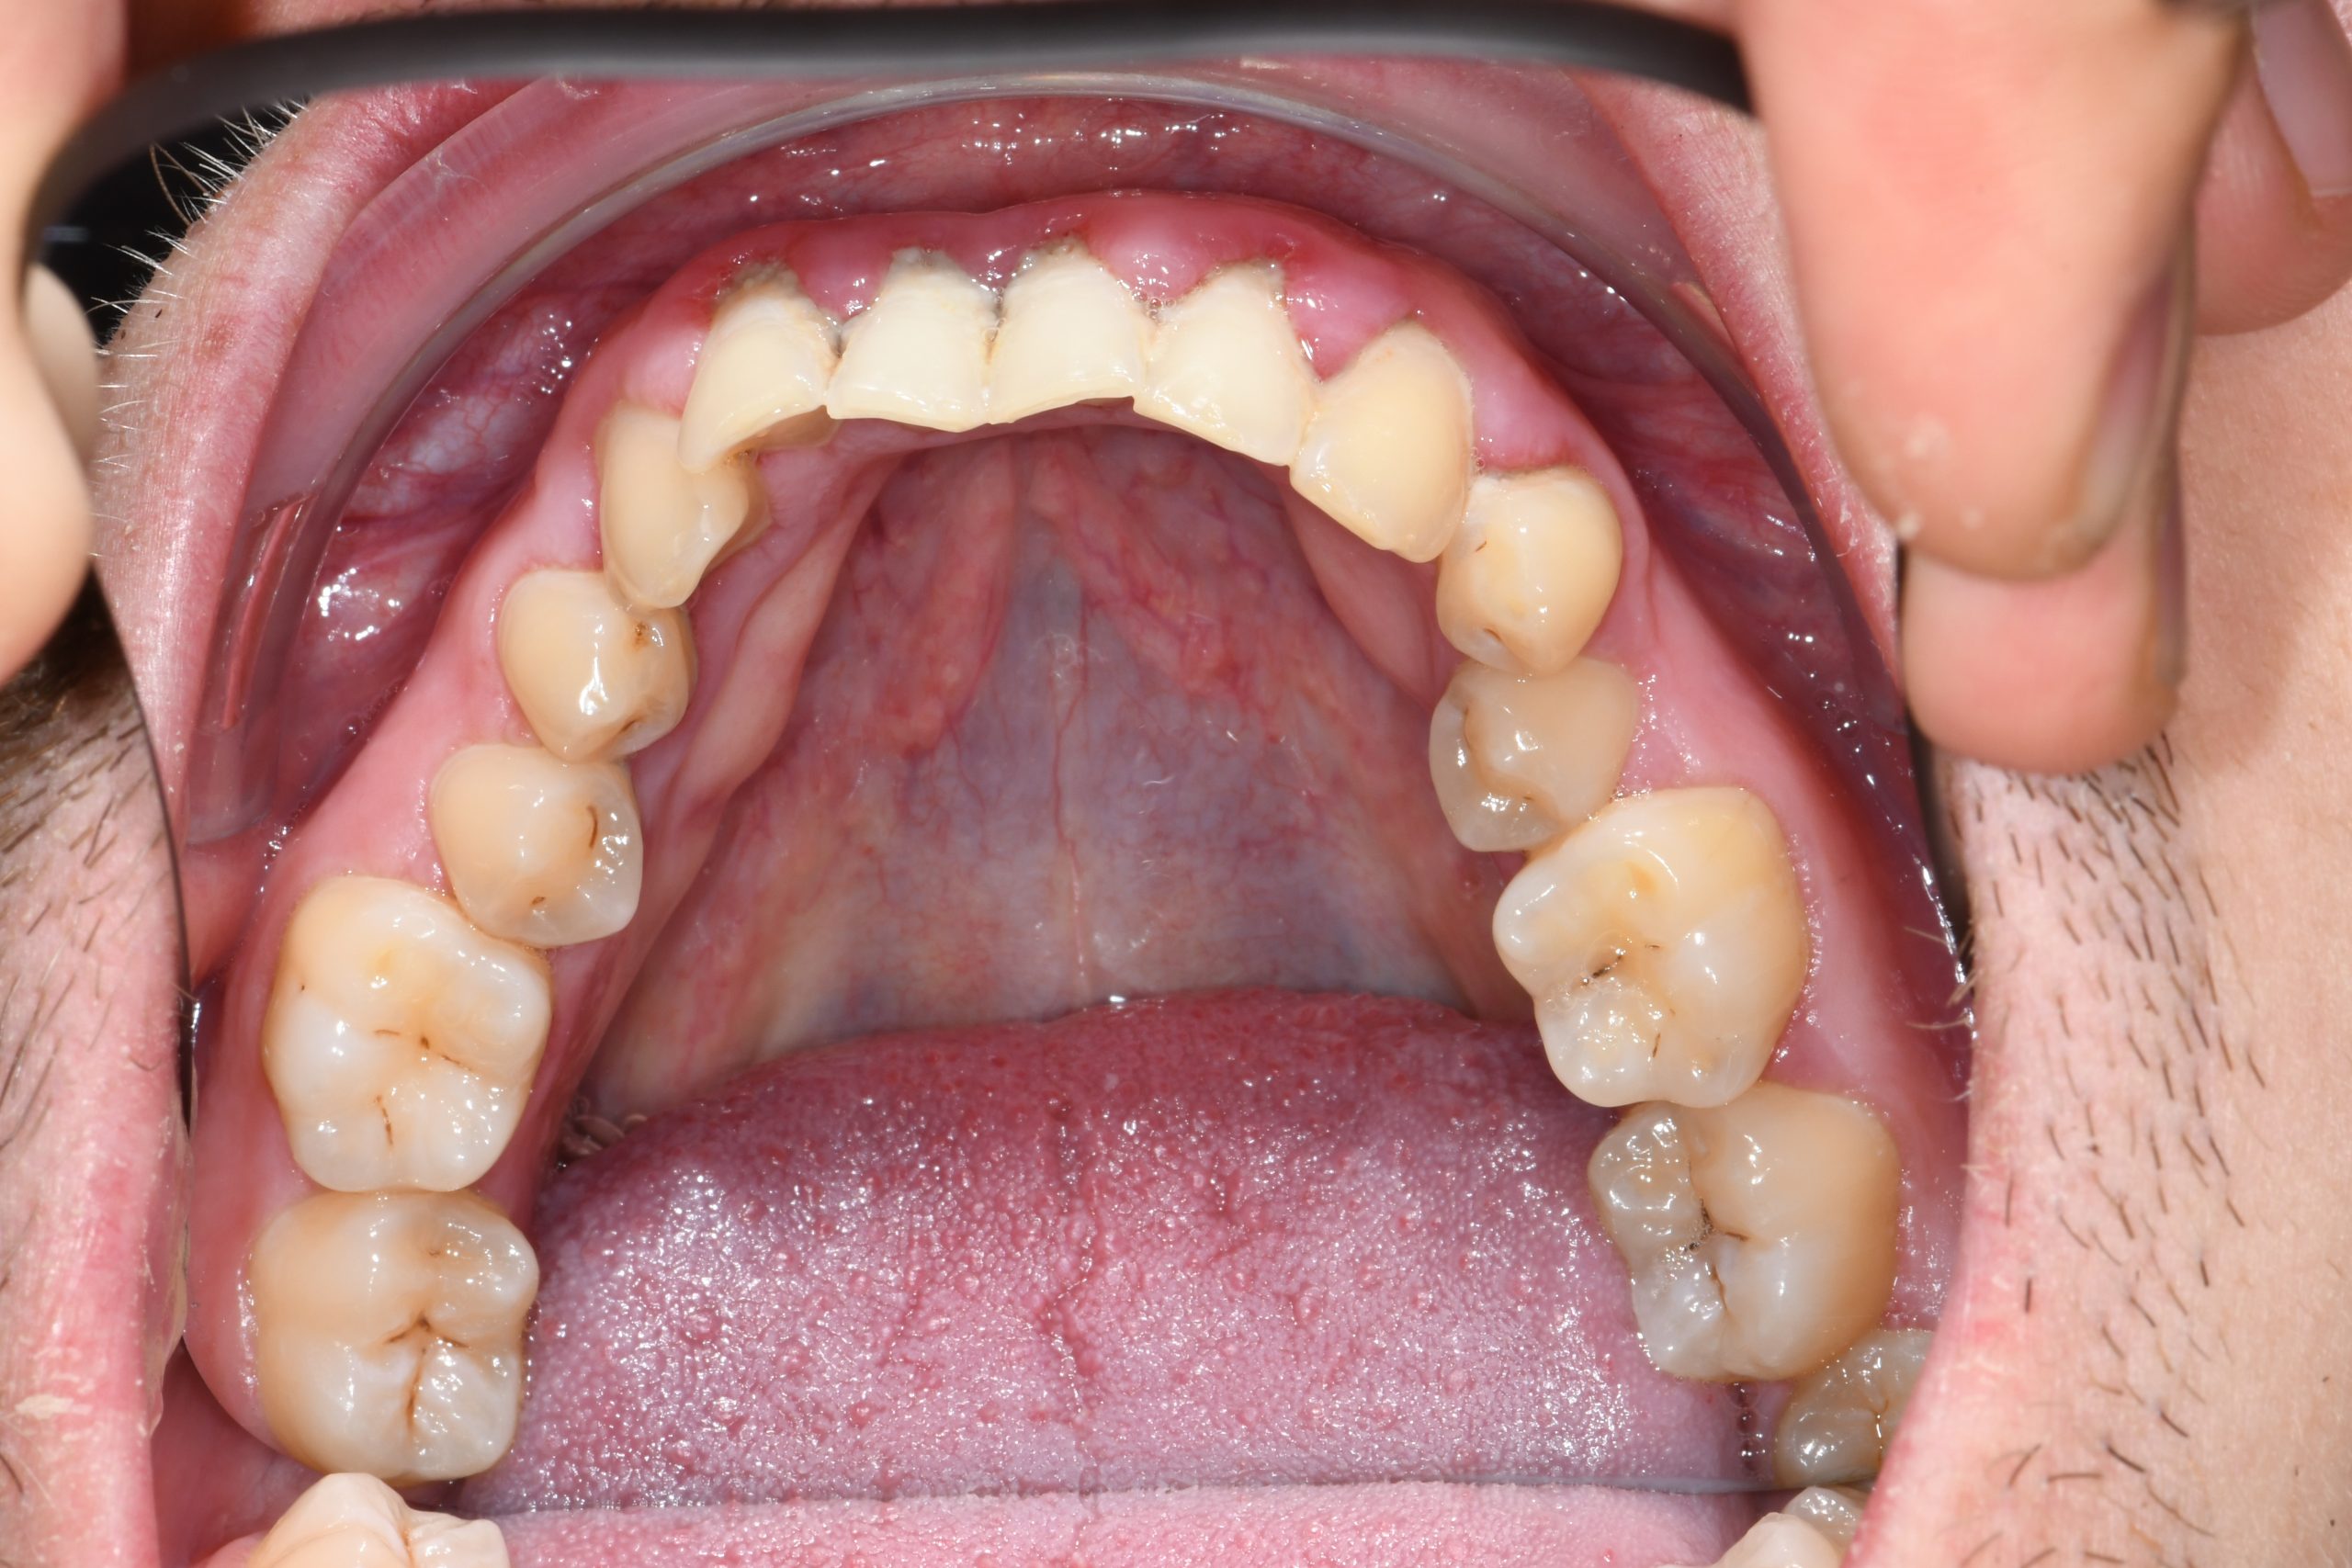

Az elmúlt évekből rengeteg szakmai referenciát tudnánk bemutatni, amelyek különböző fogszabályozási problémákat oldottak meg. Válogatva a több száz esetből, ezen az oldalon olyan képeket, információkat igyekeztünk bemutatni, amelyeknek a segítségével a jövőbeni pácienseinknek azt tudjuk üzenni: A Te fogsorod is lehet gyönyörű!

(Képeket a Pácienseink külön írásos beleegyezésével mutatjuk be!)